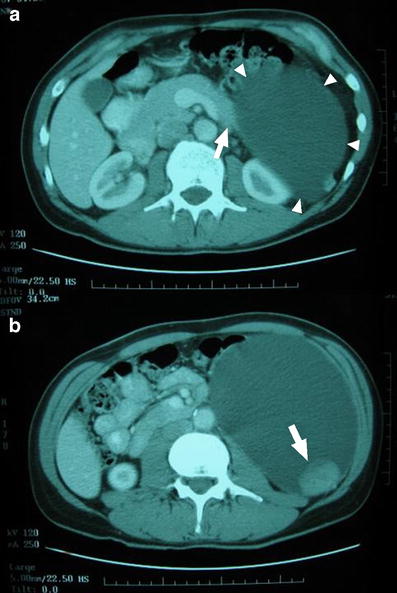

Contrast enhanced CT scan shows images of a pancreatic cyst (arrowheads) originating from the tail of the pancreas (a) and a mural nodule within the wall of the cystic mass (b)